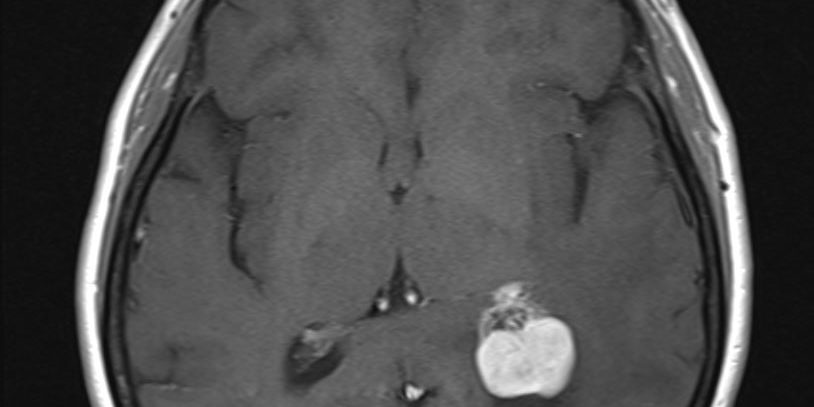

Ασθενής άνδρας, 49 ετών με επίμονες κεφαλαλγίες και τον τελευταίο καιρό και διαταραχές όρασης αριστερά.

Η μαγνητική τομογραφία ανέδειξε χωροκατακτητική εξεργασία εντός της αριστερής πλάγιας κοιλίας του εγκεφάλου.

Το συγκεκριμένο ενδοκοιλιακό μηνιγγίωμα παρουσιάζει δύο πλεονεκτήματα για τον νευροχειρουργό. Πρώτον, είναι σχετικά μικρό σε μέγεθος και δεύτερον έχει μια κύστη η οποία δημιουργεί «χώρο» τον οποίο μπορεί να εκμεταλλευτεί ο νευροχειρουργός.